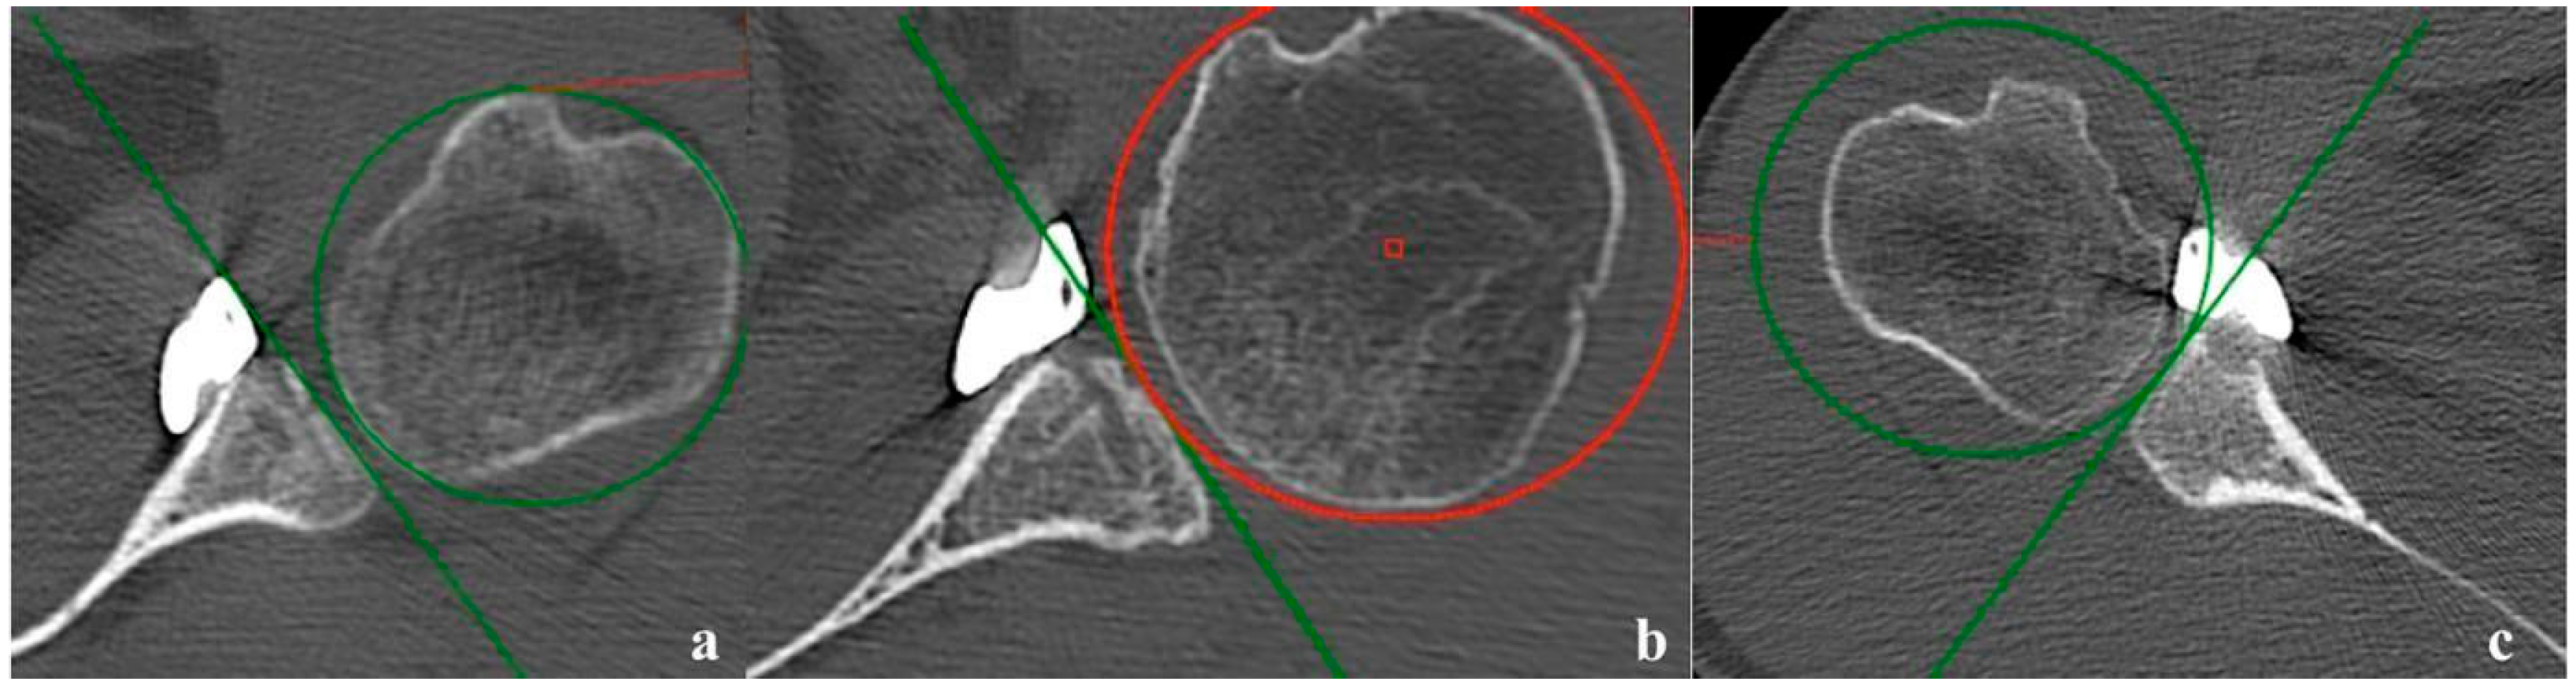

3.4. Early Radiologic Results

- Kany, J.; Flamand, O.; Grimberg, J.; Guinand, R.; Croutzet, P.; Amaravathi, R.; Sekaran, P. Arthroscopic Latarjet procedure: Is optimal positioning of the bone block and screws possible? A prospective computed tomography scan analysis. J. Shoulder Elb. Surg. 2016, 25, 69–77. [Google Scholar] [CrossRef] [PubMed]